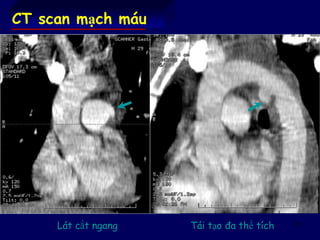

CT scan mạch máu

Lát cắt ngang Tái tạo đa thể tích

73 CT scan mạchmáu Lát cắt ngang Tái tạo đa thể tích